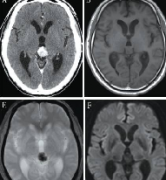

多形性胶质母细胞瘤(GBM)很少在松果体区发现。本文介绍了一个松果体区原发性胶质母细胞瘤(GBM)的病例,讨论了临床过程、影像学表现和治疗方法。根...

磁共振成像是优选的诊断技术,将海绵状血管瘤与的松果体区肿瘤区分开来。无需立体定向活检或术前盲照射。可以进行早期显微外科干预,预防复发性出...